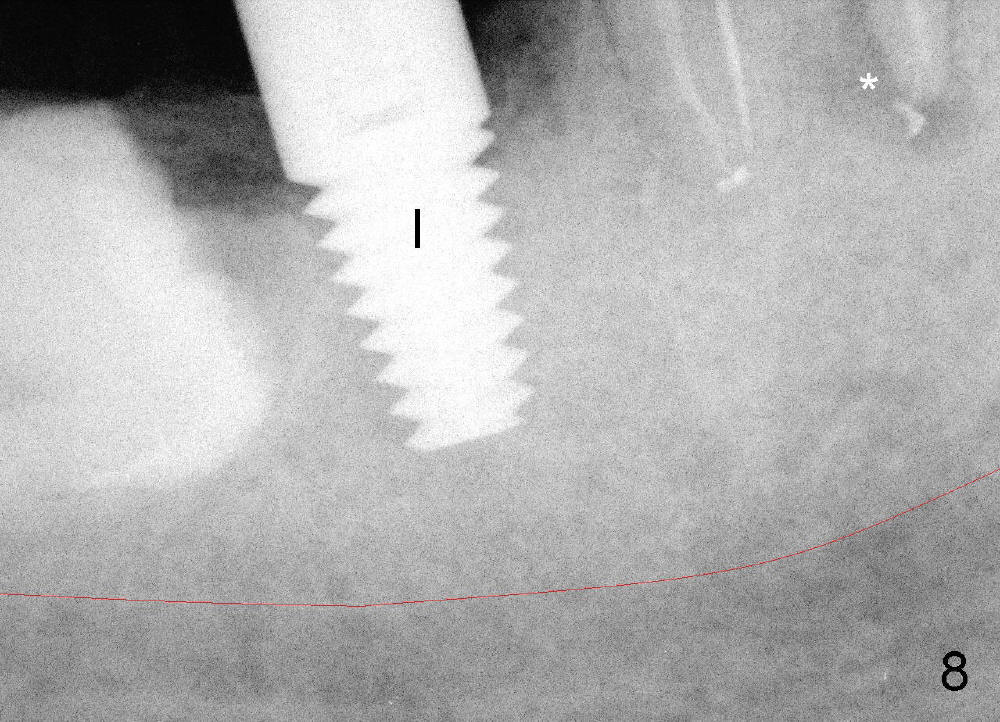

五十来岁郑先生缺失两个下颌第二磨牙,严重牙齿磨耗,三年前主诉右下第一磨牙冷热痛(可能与磨耗有关),近中有轻度根尖阴影(图一箭头),初步CT检查表明该牙齿有四个根管(图二,三),兴高采烈,这样不会错过远中舌侧根管(DL),开髓发现根管几乎阻塞,尤其是远中舌侧,hand files不容易进入根尖,使用20/.04 rotary file时,在根尖断裂(图四箭头,其余根管插入30/.06牙胶尖),一时不能bypass断针,暂封。十二天后,重新bypass断针,终于成功,但是取不出断针,扩大二十号hand file(远中舌侧根管),图五,图六侧方充填(lateral condensation)之前,图七之后(图六,七*:近中阴影)。根管治疗和牙冠之后一直无症状,一年半在第二磨牙处植牙(图八I),虽然第一磨牙近中根尖阴影增大(*),但离植牙还有一定距离,可能不会产生问题。不过不久植牙松动,病人自己取出,可能当时钻洞太大,而不够深(no primary stability),怕侵犯下颌神经(图八红线)。十个月后再次试图植牙(图九D:钻头),突然发现智齿(阻生)在手术视野之中,而且智齿咬合面不干净,结果取消植牙,把智齿拔除,这时病人第一磨牙仍没有症状,但是根尖阴影不可观(图九*),远中舌侧根尖好像没有病变(箭头)。大概这次智齿拔除也与左下智齿七拔除(左下第二磨牙植牙之前)一样不舒服,郑先生一直没有回来做右下第二磨牙植牙。上周六他终于登门,右下第一磨牙出现根尖脓肿症状(术后近三年),根尖片如图十。S代表已经愈合智齿牙槽窝,根尖阴影不小,断针根尖仍没有阴影。